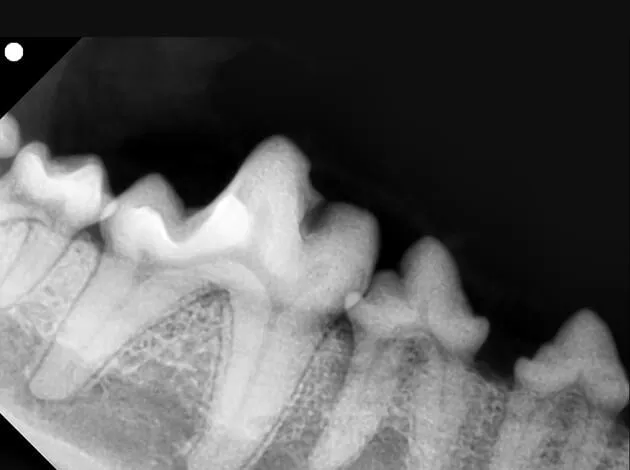

通常のレントゲンと歯科用レントゲンでは、得られる情報に大きな差があります。

通常のレントゲンは、無麻酔で撮影ができ、全体像を捉えられるメリットがありますが、歯を撮影すると、左右の歯が重なり合って写るため、どうしても観察できない部分が出てきてしまいます。

歯科用レントゲンは、歯の根の部分や、歯髄と呼ばれる歯の内部、顎の骨の状態までを精密な画像で撮影することができます。歯の1本1本の細部までをしっかり観察することができるため、病状をより正確に把握して、適切な診断、治療、予後判定につなげることができます。

たとえば、歯周病であれば、重症度を診断するのに有効です。歯の根の状態を見て抜歯が必要かどうかを判断できますし、継続して治療を行う場合は、経過観察にも役立ちます。

歯科用レントゲンでわかる異常

歯科用レントゲンで撮影すると、歯の周囲の部分が黒く写っていることがあります。これは、悪くなった歯の根が歯周病により溶け始めていることを意味します。つまり、抜歯が必要な状態です。

抜くべき歯を放置しておくと歯周病がますます進行し、やがて歯が抜け落ちるだけでなく、炎症が鼻まで進んで顔から血膿が出てきたり、眼の下に膿がたまったり、顎の骨が折れたり、本当に可哀想な状態になってしまうことも少なくないからです。

歯科用レントゲンの画像があれば、抜歯を含む歯周病の治療方針を迅速に決めることができ、飼い主様も診断の根拠となるお口の状態を一緒に確認することができます。